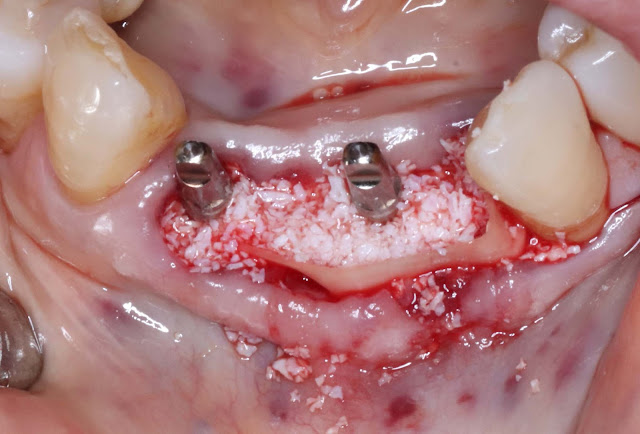

First, the tooth was extracted and waited for about 3 months.

Bone grafting was performed simultaneously on the buccal side using allogeneic bone, xenogeneic bone, and absorbable membrane.